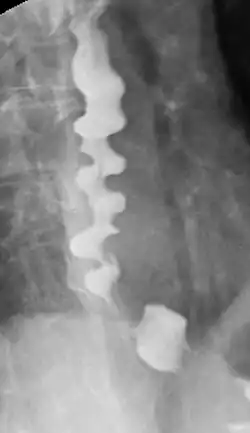

Bei der Röntgendiagnostik kommt das Ösophagus-Breischluck-Verfahren zum Einsatz. Dabei schluckt der Patient ein Barium-haltiges Kontrastmittel, von dem während der Passage durch die Speiseröhre ein Röntgenbild erstellt wird. Auf diese Weise können Divertikel, Einengungen, die Längsausdehnung von Tumoren und der Ablauf des Schluckvorgangs (und damit auch Störungen und Reflux) sichtbar gemacht werden.[40]